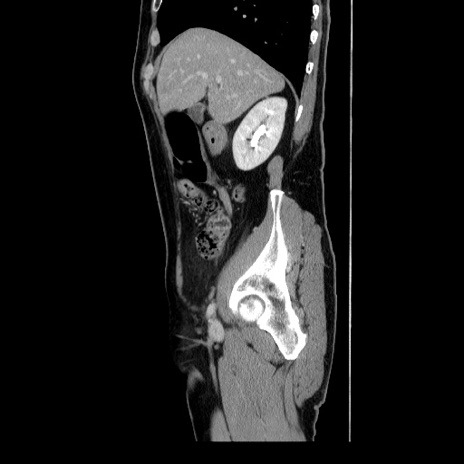

冠状断像

【症例】60歳代 男性

【主訴】右鼠径部膨隆

【現病歴】1年程前より右鼠径部膨隆あり。自己にて還納可能だったため放置していた。3時間前より右鼠径部の脱出を認め、還納困難となり受診。

【身体所見】右鼠径部に小児頭大の膨隆あり。弾性硬であり、用手還納は困難。左鼠径部にも膨隆を認める。脱出はなし。